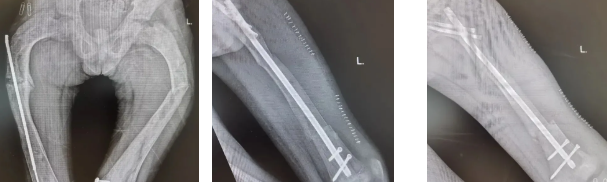

每次提起巴旦,他的父亲都是愁容满面。巴旦患有多发骨纤维结构不良,双侧股骨扭曲变形,多次骨折,多次手术,都不能让他重新站立起来。这次从当地医生那里听说北京积水潭医院可以治疗,抱着最后一丝希望,不远万里来到北京。因为已经经过4次大手术,巴旦入院后很拘谨,陌生的地方,陌生的人,他不知道会不会像以前一样,满怀希望而来,失望而去。

对于病人来说,术前的等待是艰苦而漫长的;对于医师来讲,是紧张而有序的。经过科室讨论,决定采用多段截骨矫形,逆行扩髓,带锁髓内针固定术对巴旦进行治疗。经过4个小时的操作,手术圆满完成,术后恢复顺利。巴旦的脸上展露出久未绽放的笑容,对以后的生活充满希望!